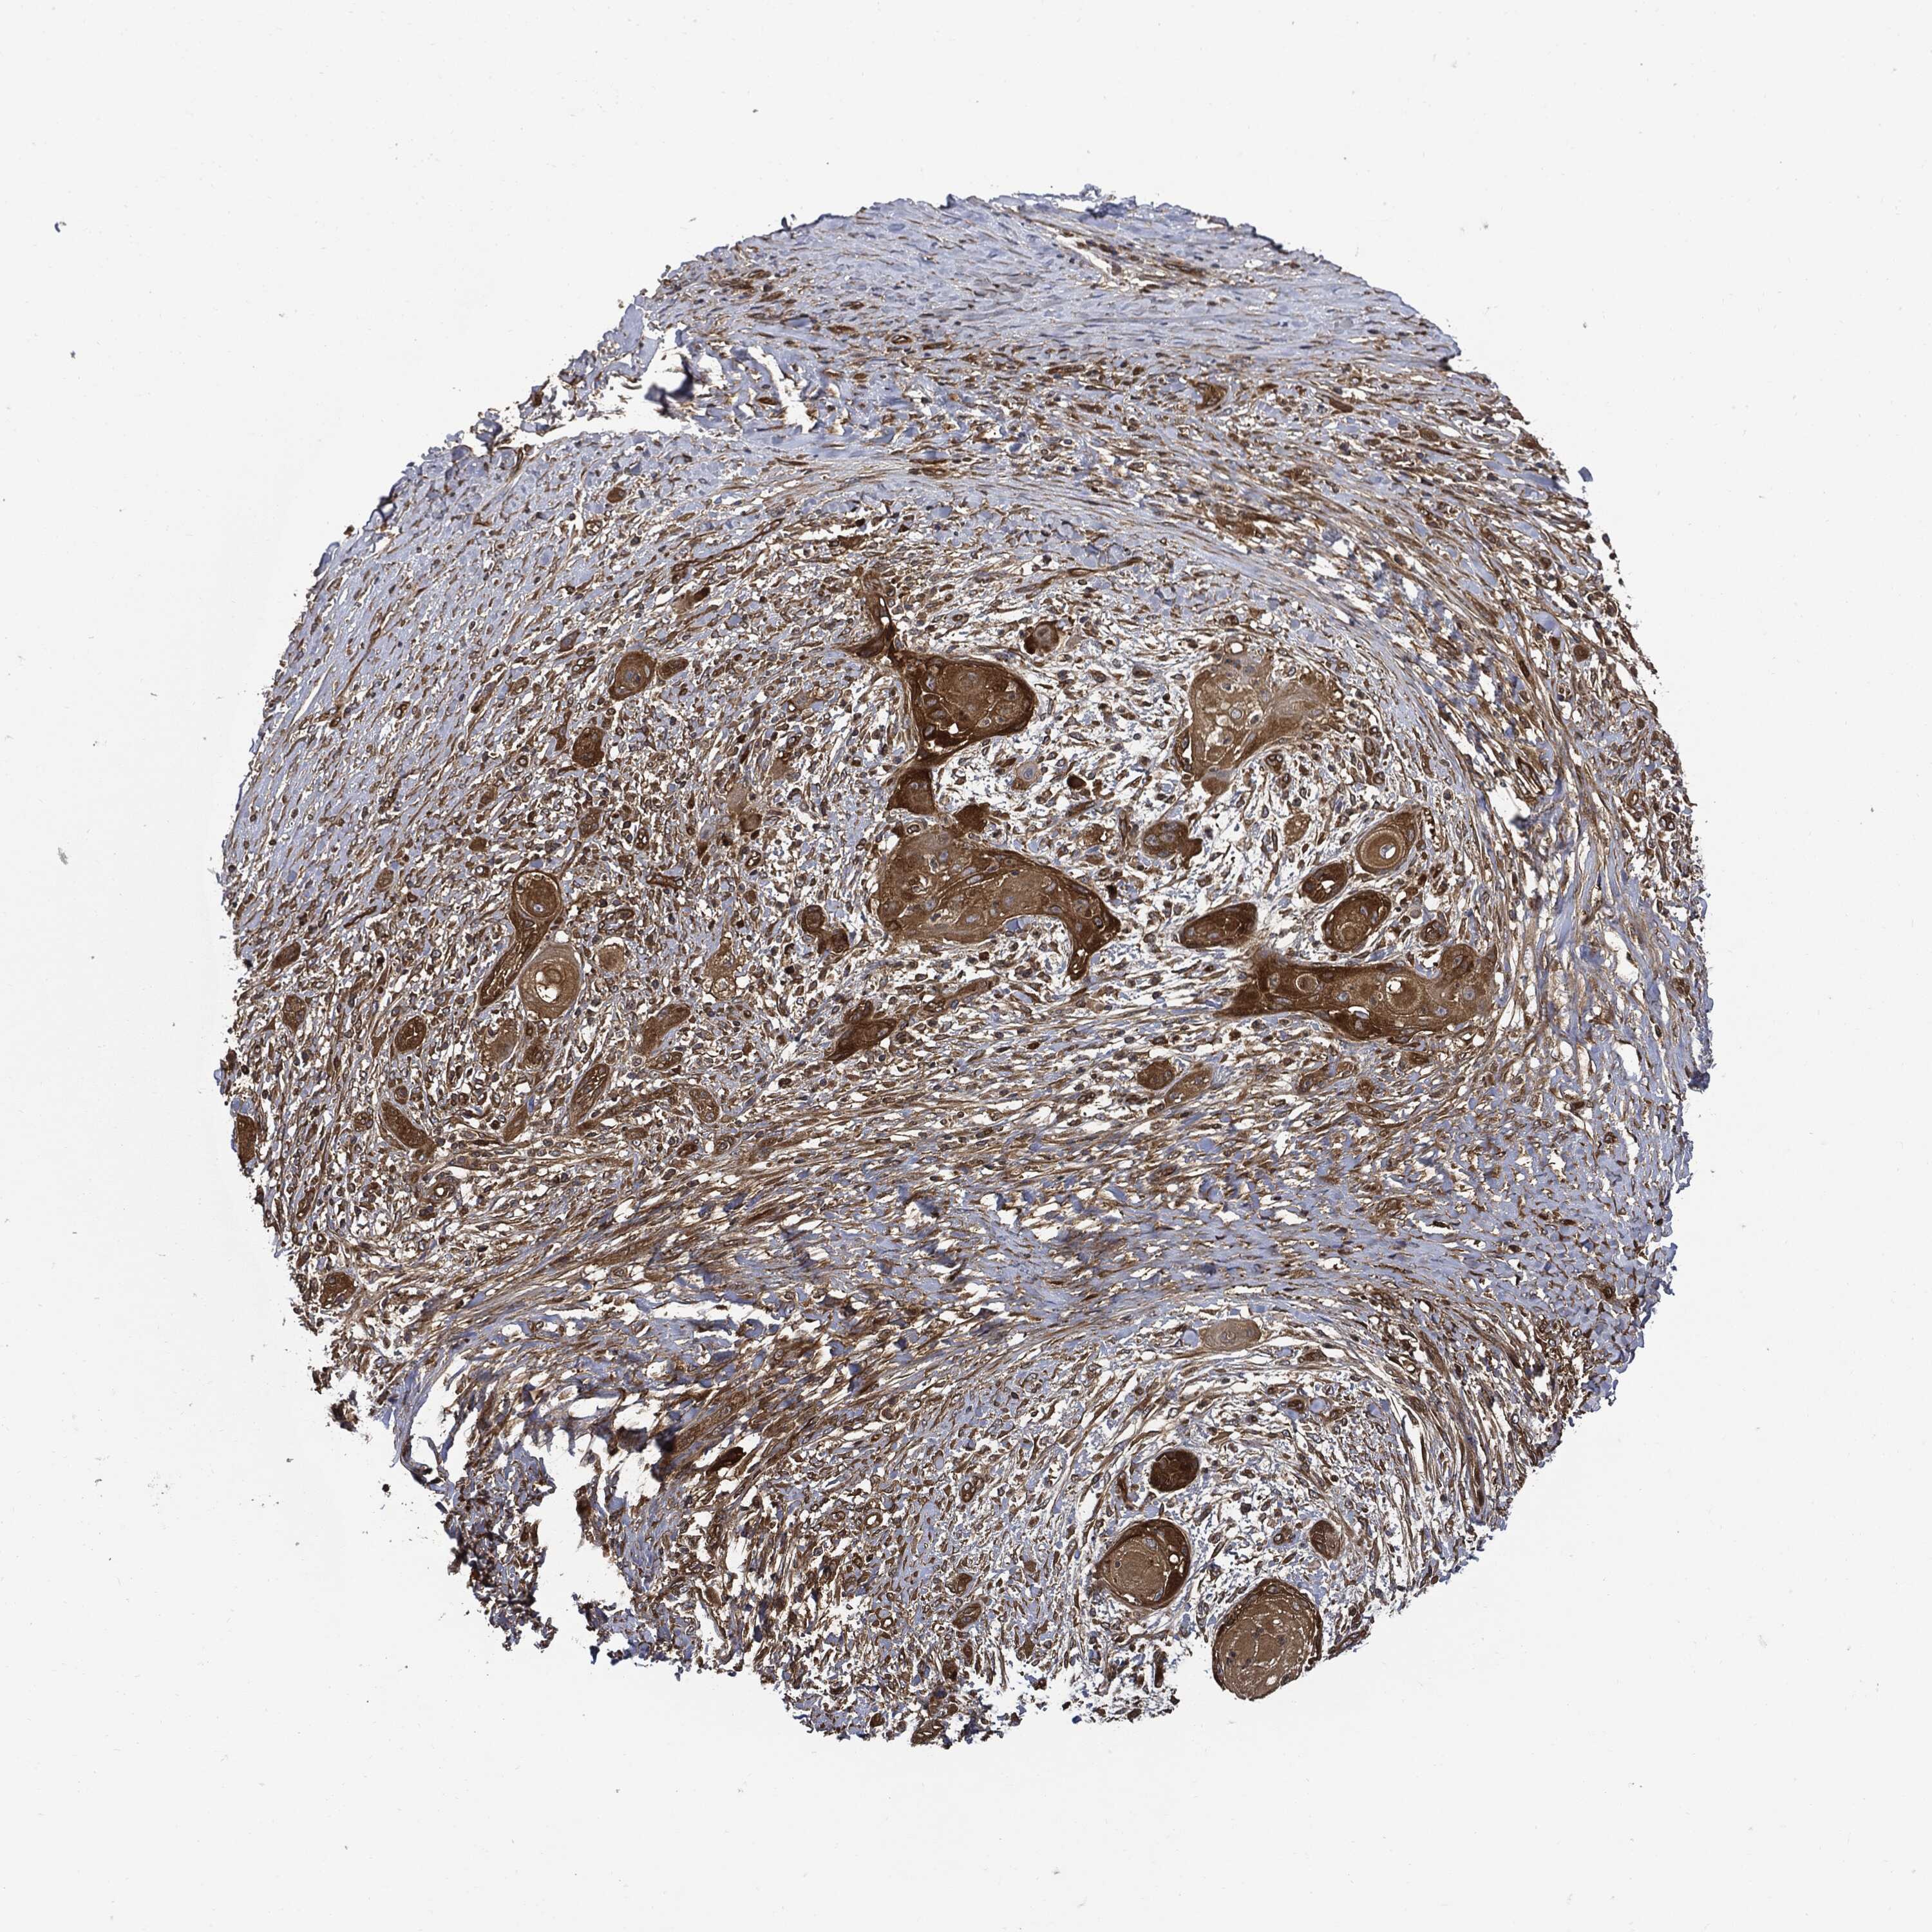

CANCER SKIN CANCER Show tissue menu

Basal cell and squamous cell cancer

SKIN CANCER - Protein expressioni

A mouse-over function shows sample information and annotation data. Click on an image to view it in a full screen mode. Samples can be filtered based on level of antibody staining by selecting one or several of the following categories: high, medium, low and not detected. The assay and annotation is described here.

Each image is clickable and will lead to virtual microscopy that enables deeper exploration of all samples and also displays staining intensity scores, fraction scores and subcellular localization as well as patient and tissue information for each sample.

HPA030419

HPA030420

HPA030422

CAB025196

CAB080286

CAB080287

Basal cell carcinoma

Squamous cell carcinoma, NOS

Squamous cell carcinoma, metastatic, NOS